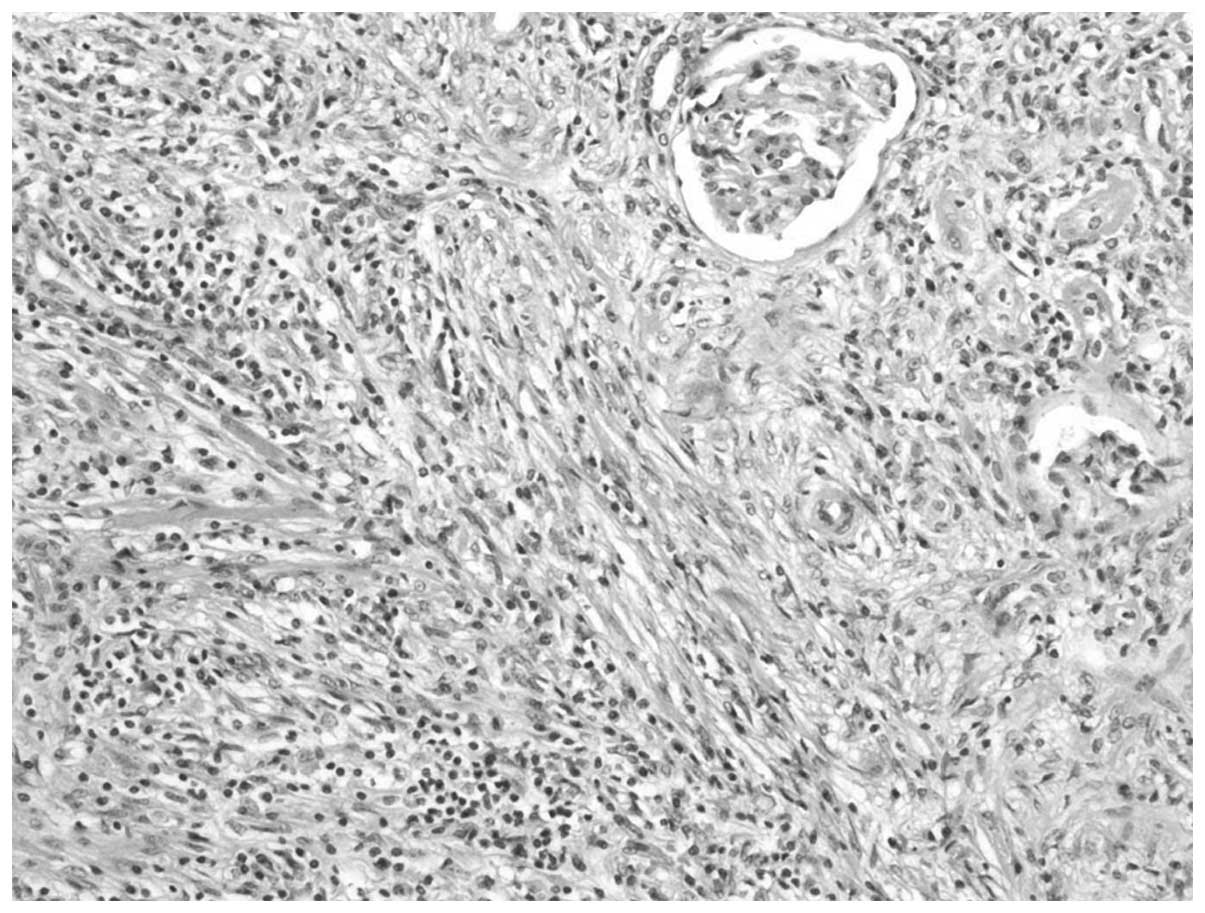

A 48-year-old female visited the First Hospital, Jilin University (Jilin, China) for routine check-up for hepatitis B on July 19, 2012 and presented with no symptoms. The patient had a history of trauma to the left hypochondrium 13 years previously and a history of hepatitis B for 20 years. The latter developed into hepatic cirrhosis, hypersplenism and coagulation disorders. The physical and basic paraclinical examinations were normal. Blood tests revealed a leukocyte count of 2850/mm3, a hemoglobin count of 5.6 g/dl, a platelet count of 6700/mm3, a urine leukocyte count of 20.1/HPF and a urine erythrocyte count of 2.5/HPF. The thrombin time was 19.4 sec and the prothrombin time was 14.0 sec. The international normalized ratio was 1.21, the prothrombin ratio was 1.22 and the prothrombin activity was 69%. Clinical laboratory measurments revealed the following levels: Serum fibrinogen, 0.55 g/l; hepatitis B virus surface antigen (HBsAg), 197.260 IU/Ml; hepatitis B virus e antigen, 0.299S/CO; hepatitis B virus e antibody, 0.110S/CO; and hepatitis B virus core antibody, 18.210S/CO. An abdominal ultrasonography revealed a 1.4×1.4-cm-sized mass with an obscure boundary in the upper pole of the kidney, which protruded through the surface. The computed tomography (CT) scan revealed a 1.6×2.9×2.0-cm lesion in the upper pole of the kidney. The CT was slightly enhanced with contrast (Fig. 1). The magnetic resonance imaging revealed a heterogeneous mass measuring 2.6 cm, showing low intensity on the T1-weighted images and high intensity on the T2-weighted images, which was accompanied with hypointensity that surrounded the center of the lesion (Fig. 2). A radical nephrectomy was performed. The histopathological examination resulted in the lesion being diagnosed as an IMT, in which spindle cells were admixed with variable amounts of extracellular collagen, lymphocytes and plasma cells (Fig. 3). Immunostaining was positive for vimentin and focally positive for smooth muscle actin, desmin and Ki-67 (Fig. 4). There was no evidence of recurrence during a follow-up period of six months.

Figure 3

Photomicrograph showing bands of spindled fibroblast-like cells and collagen with infiltrating lymphocytes and plasma cells (HE staining; magnification, ×200).